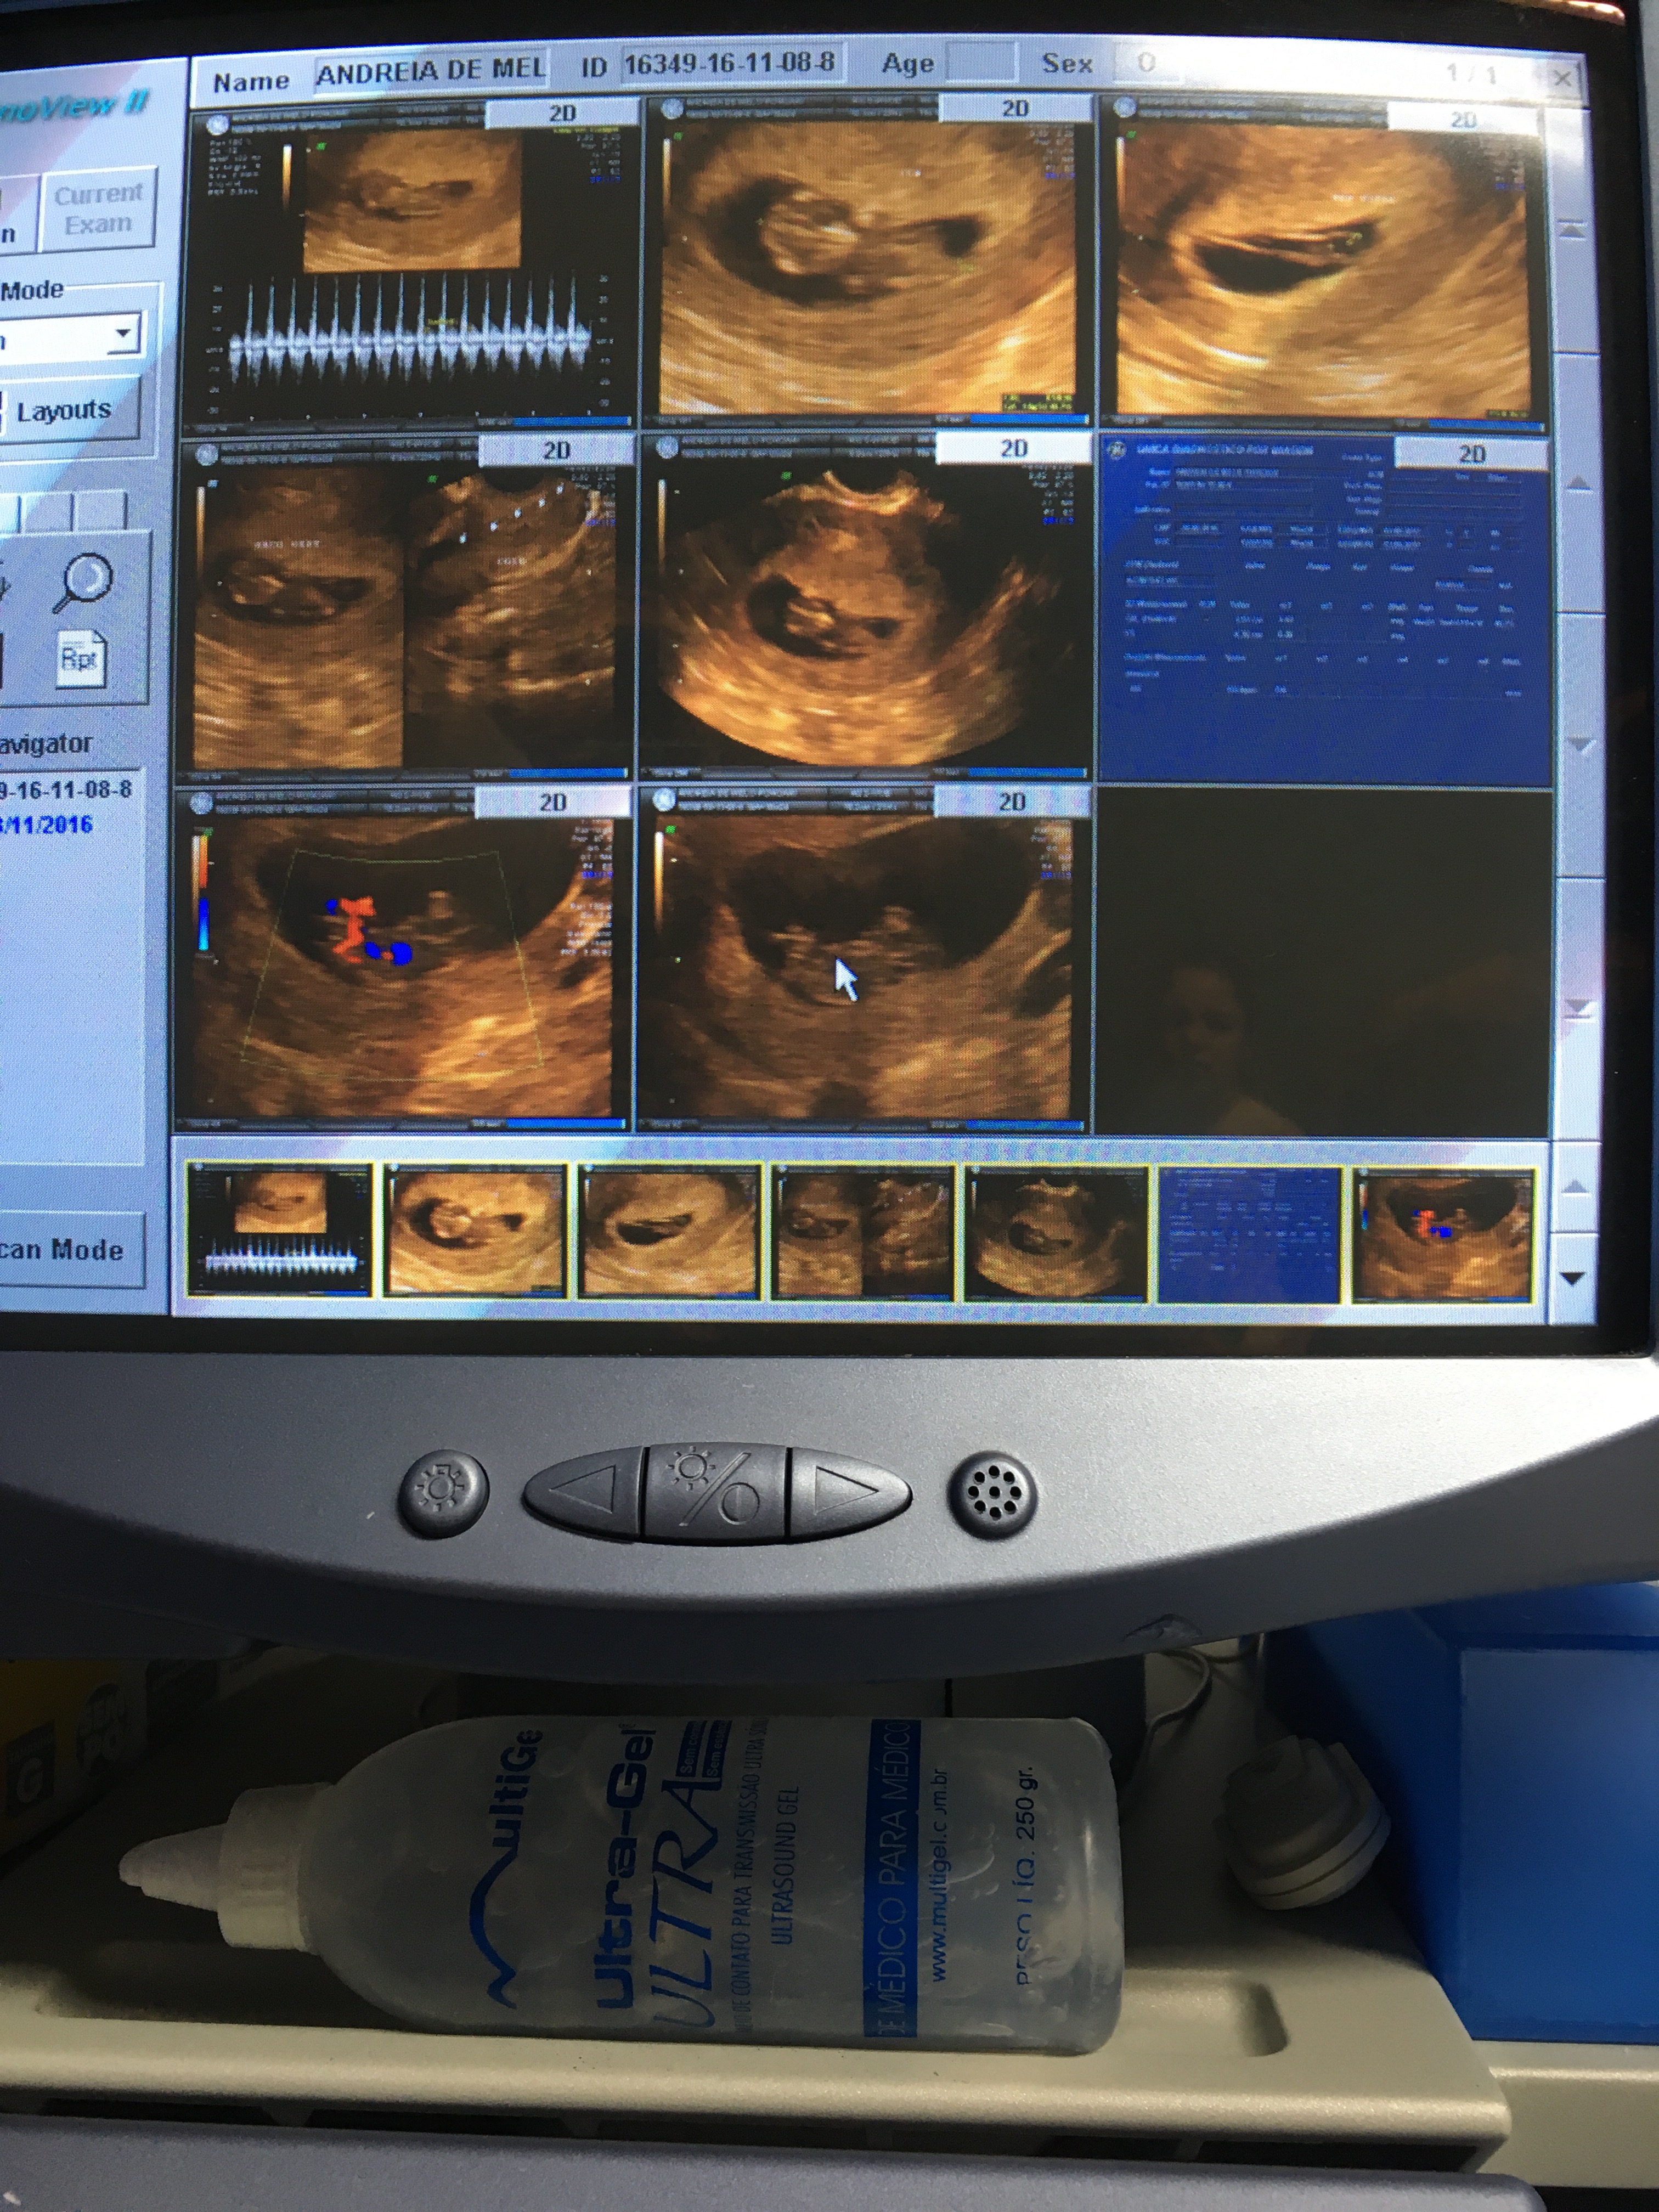

Há 4 anos… um momento incrível na vida de qualquer pessoa! Relembrando:

Tem algo mais gostoso do que ouvir pela primeira vez o coraçãozinho do seu nascituro?

Escutamos o do nosso (a) segundo (a) filho (a). A emoção, claro é indiscritível!